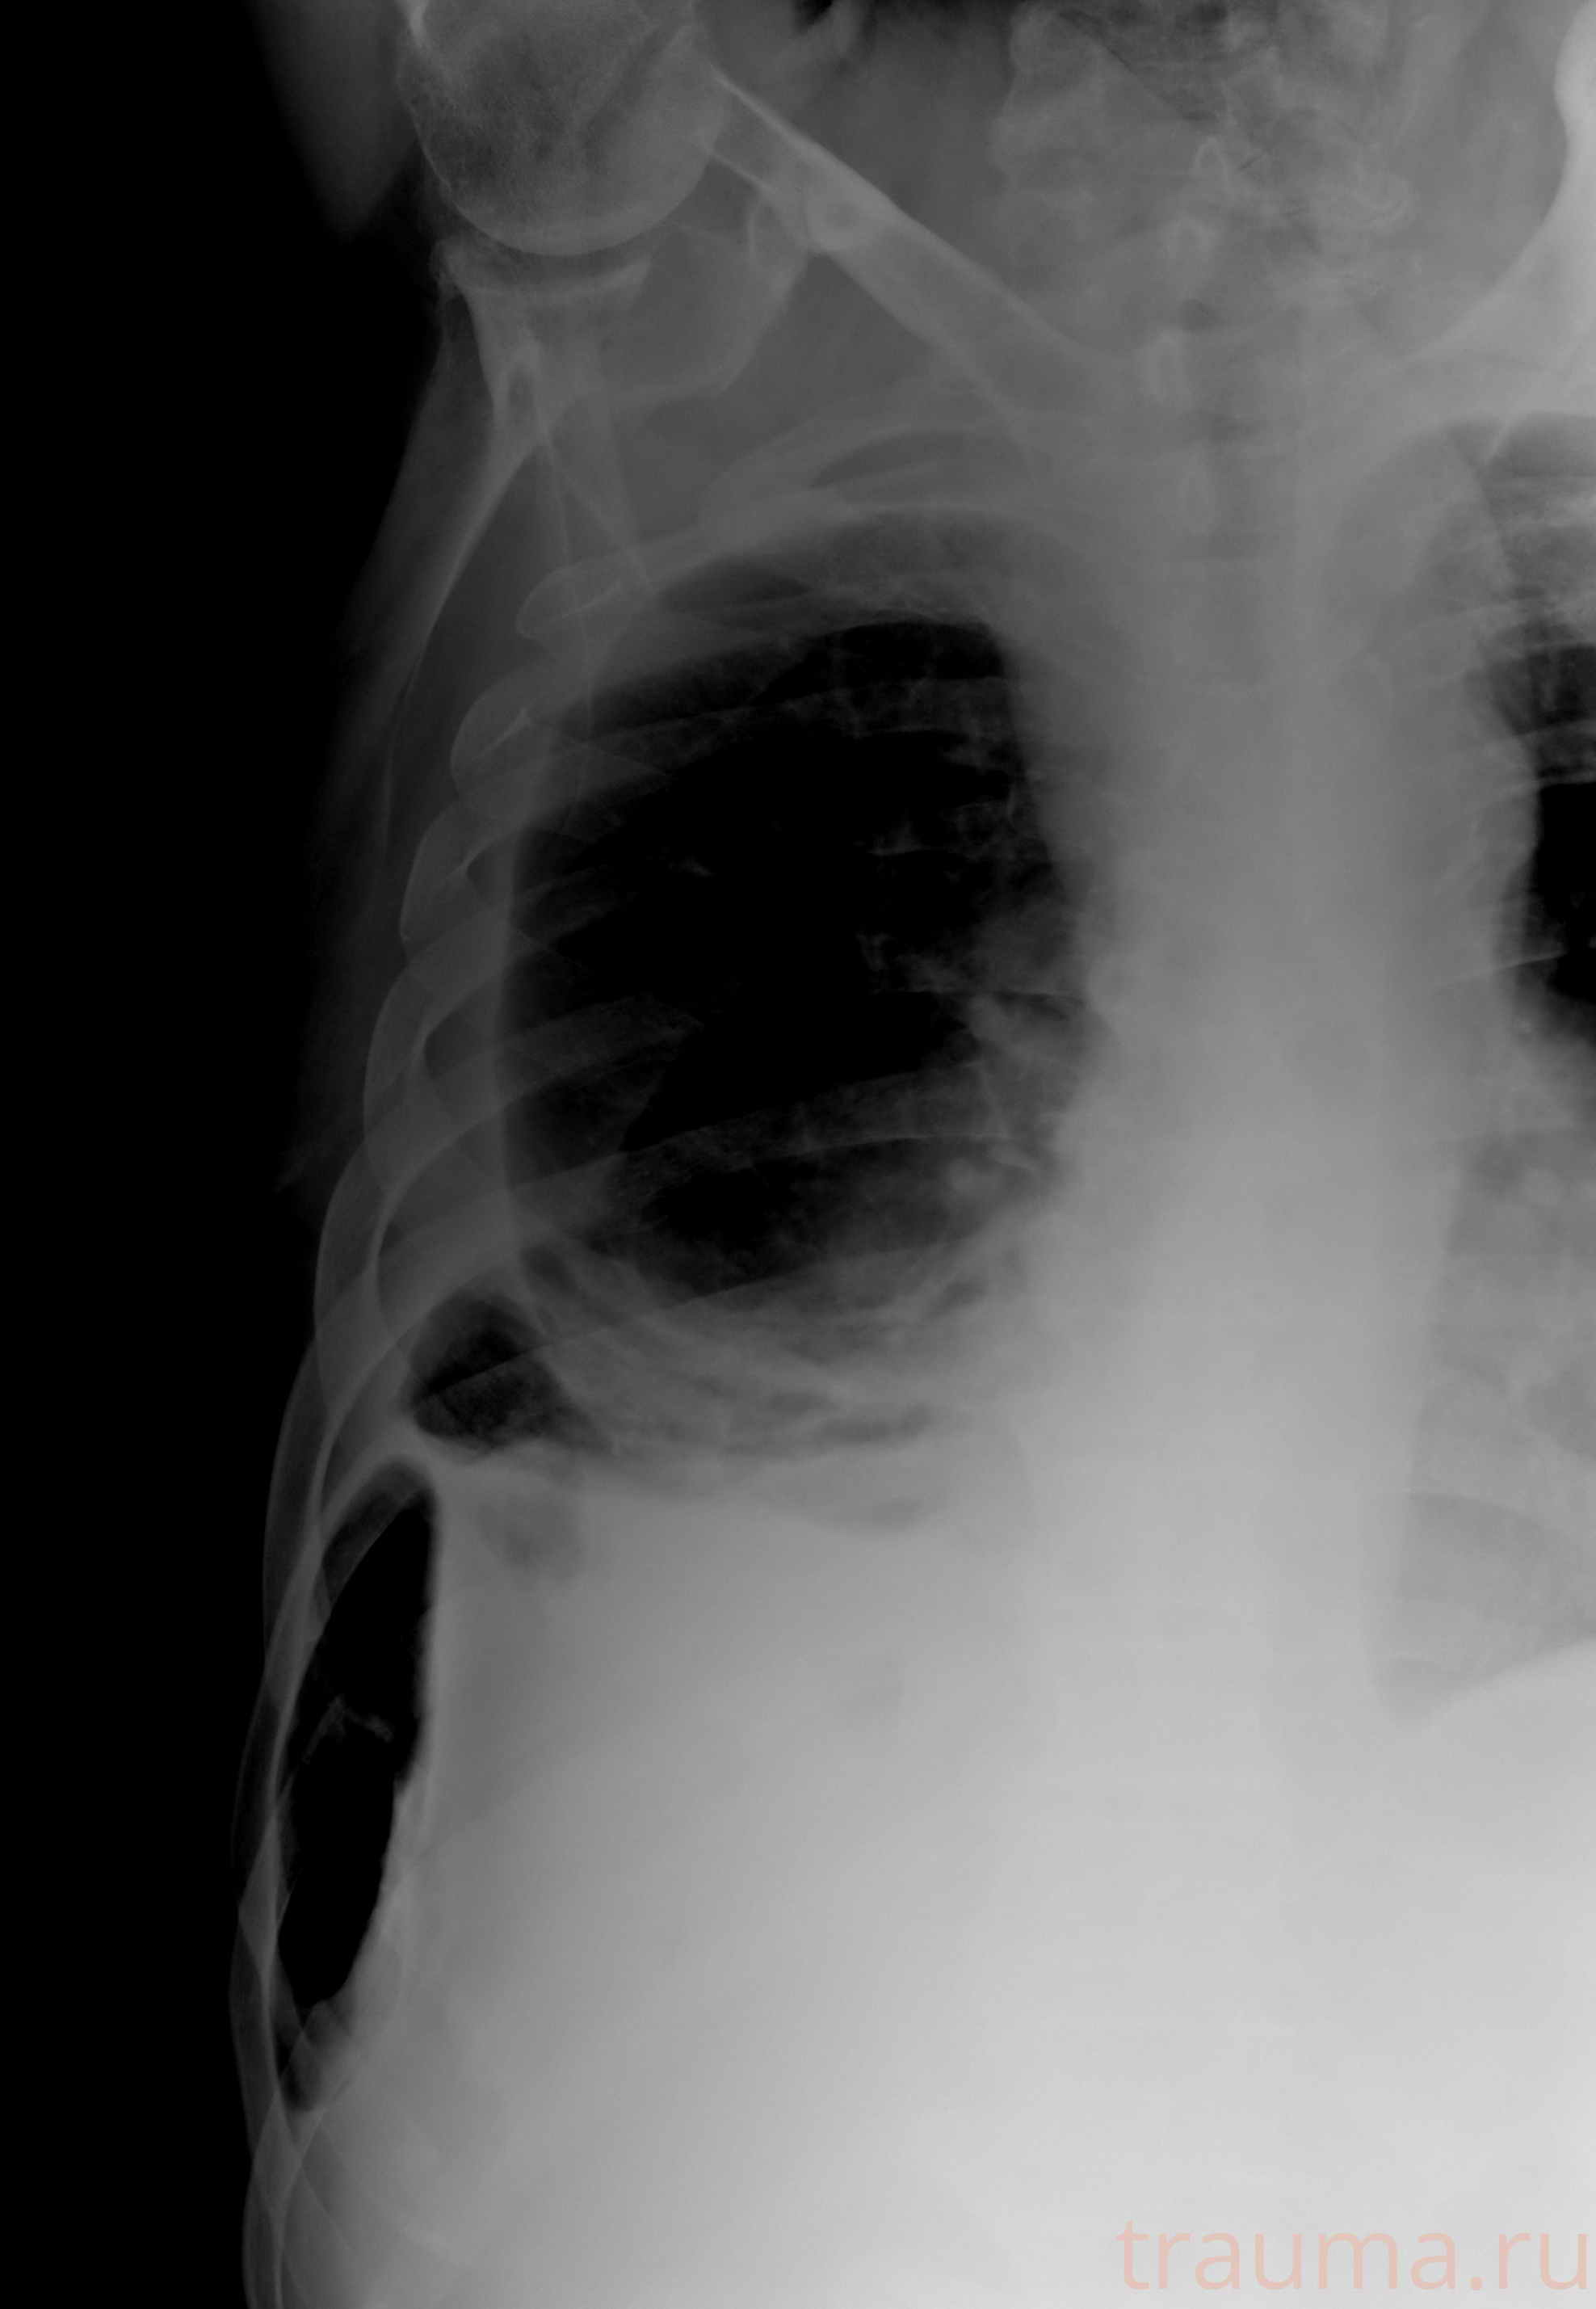

Рентген на дому: по вашему адресу приезжает врач-рентгенолог, травматолог-ортопед с мобильным рентгеновским аппаратом, проводит диагностику травмы или заболевания, делает необходимые рентгенограммы, дает рекомендации по дальнейшему лечению. Получить качественные снимки в домашних условиях возможно благодаря уникальной методике, разработанной МосРентген Центром для института  Склифосовского